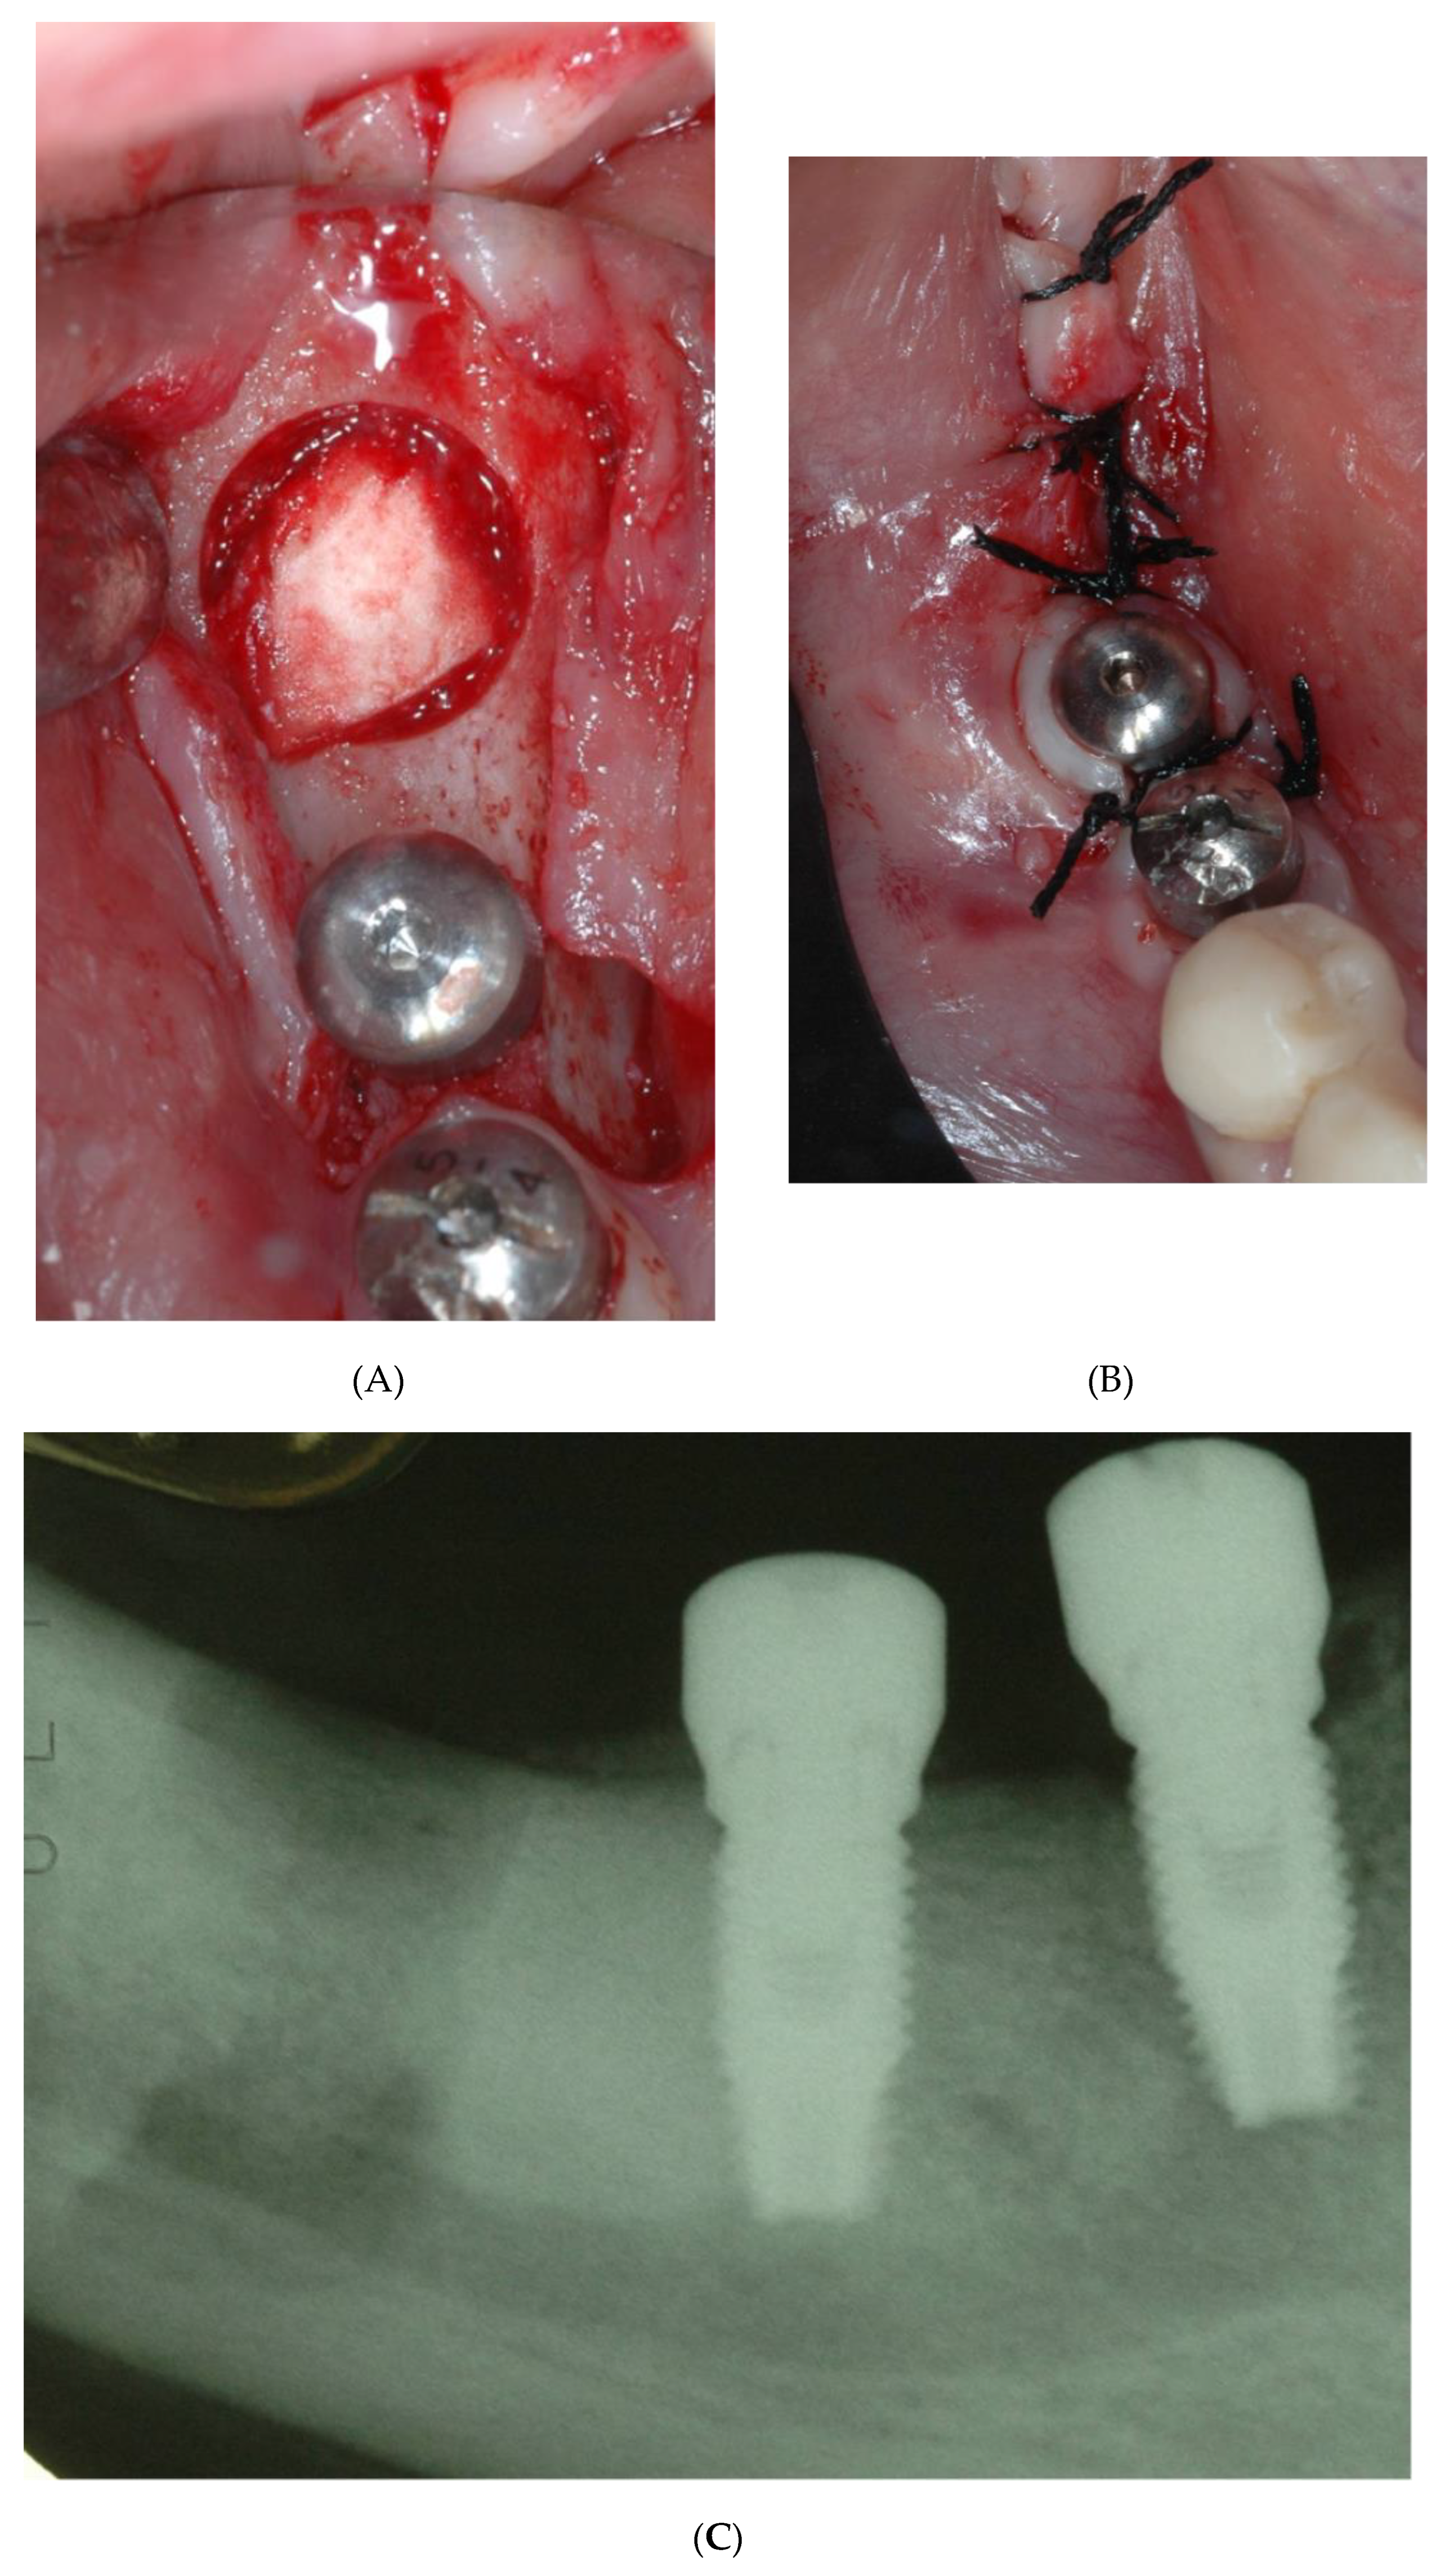

2. Case Report n.1